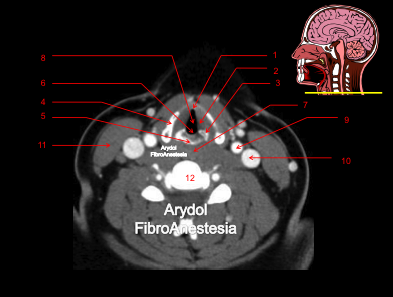

CORTE A NIVEL DE LOS SENOS PIRIFORMES Y PIE DE LA EPÍGLOTIS

1.cara laríngea de la epíglotis (pie de la epiglotis); 2.cartílago tiroides (lámina no osificada); 3.músculo esternocleidomastoideo; 4.músculos prelaríngeos; 5.repliegue ariepiglótico; 6.senos piriformes derecho e izquierdo; 7.luz laríngea; 8.arterias carótidas interna y externa; 9. vena yugular interna; 10.músculo constrictor faríngeo; 11.vértebra